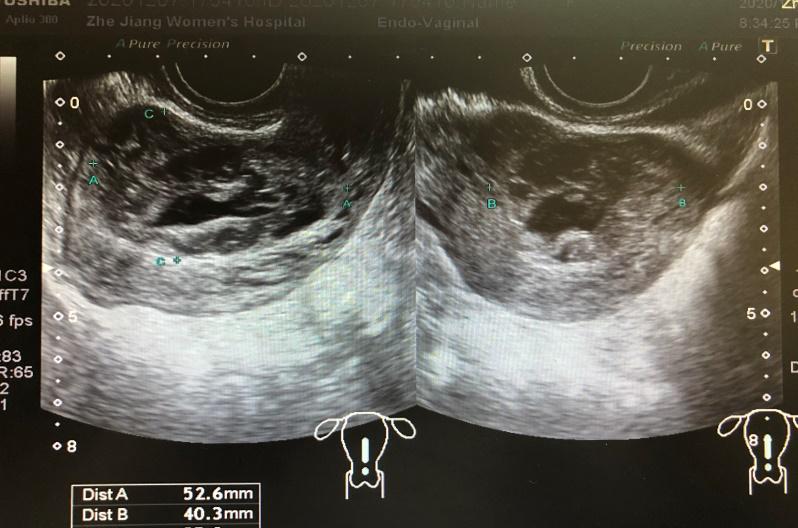

我院阴道超声: 子宫前位,大小6.2*5.8*5.6cm,宫腔线显示不清,宫腔至前壁见范围约5.3*4.0*3.5cm不均回声,部分边界欠清,周边见较丰富血流信号,RI:0.42,呈动脉频谱。前壁浆膜层菲薄,余宫壁回声尚均匀。双卵巢正常大,回声无殊。诊断结果:子宫增大,宫腔至前壁不均回声,请结合临床。